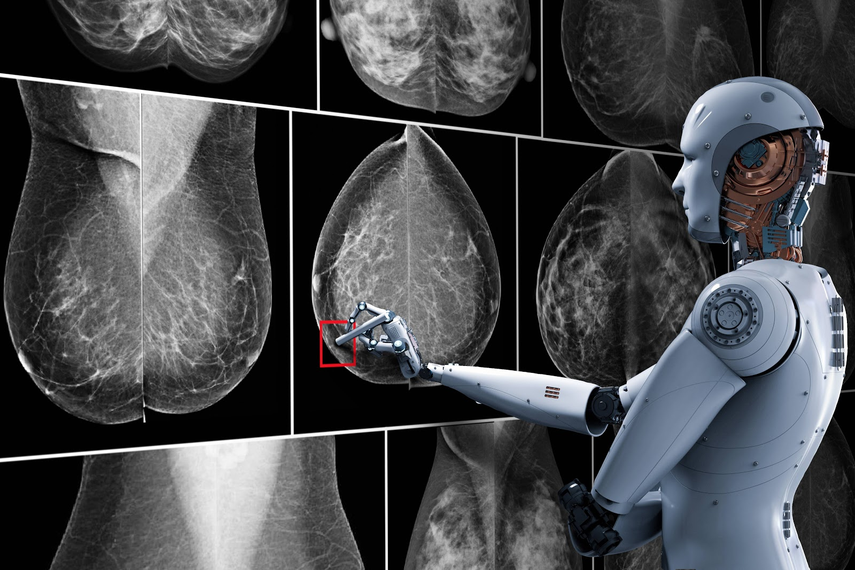

Un estudio publicado este miércoles, muestra que un programa de Inteligencia Artificial (IA) parece capaz de reducir la carga de trabajo de los radiólogos en la detección del cáncer de mama, aunque es demasiado pronto para concluir sobre su eficacia, el mismo fue realizado en Suecia y publicado en The Lancet Oncology.

Este estudio concluye también que no hay riesgo de que los radiólogos utilicen software de inteligencia artificial (IA) para orientar mejor sus análisis; los investigadores dividieron a unas 80.000 mujeres en dos grupos de tamaño similar.

Todas ellas realizaron una mamografía, pero el primer grupo se cribó de forma convencional, es decir con la mirada de dos radiólogos independientes, mientras que los datos del segundo fueron examinados primero por una IA y luego por un solo radiólogo.